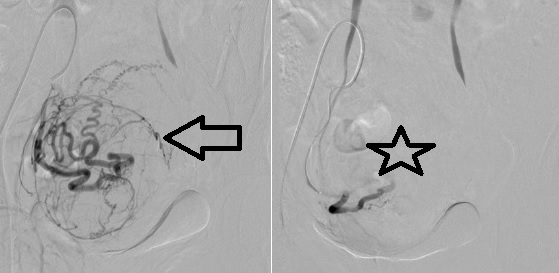

Hình 4: Minh họa động mạch tử cung và u xơ trước sau nút mạch chọn lọc |